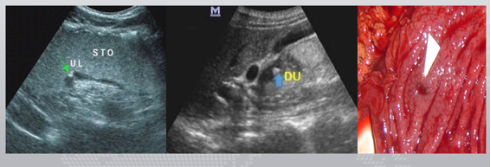

超声图像,箭头所指,低回声结节,无蒂,呈丘状,表面光滑,起源于粘膜层。

胃造影用的是什么机子胃肠超声造影--无创、无痛、无辐射!_https://www.jmylbn.com_新闻资讯_第12张

胃镜取材活检,病理证实为增生性息肉。

超声显示胃窦后壁肌层内低回声肿块,

胃镜无法探查到肿块。

最终手术结果为胃间质瘤。